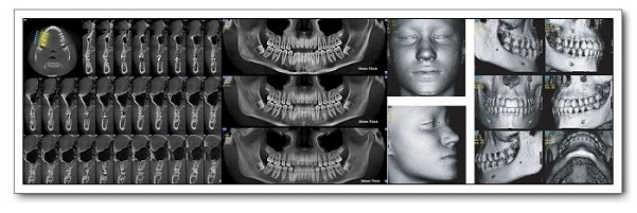

口腔影像科简介

新疆医科大学附属口腔医院影像科是拥有多台先进数字化医学影像设备和较高专业技术水平的口腔影像专业化科室。新疆医科大学口腔医院影像科现有医护人员7名。具有硕士以上学历人员占比50%科室现有原装进口的德国口腔signora锥形束CT机一台,卡瓦Aero-X三合一一台,芬兰instrumentarium数字化曲面体层摄影机1台,卡瓦RVG一台,美国柯达数字rvg一台。主要开展医疗项目有对口腔颌面部囊肿、肿瘤、外伤、炎症、颞下颌关节、涎腺、牙体...查看详情 >